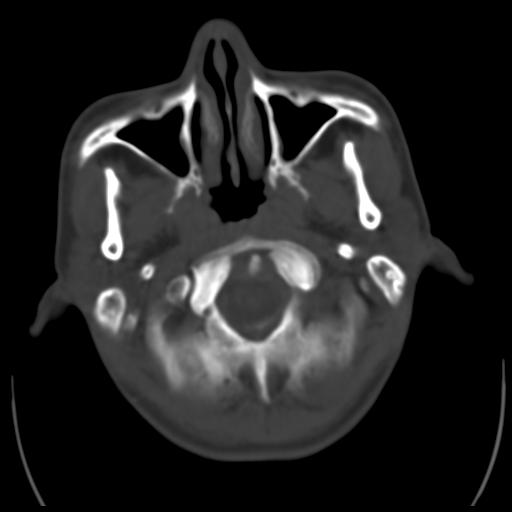

35m 鼻子时不时流血,头及右侧面部痛,颈部淋巴结未见明显大

这个东西大家仔细看看呀

蝶窦,后组筛窦及鼻咽部团块状软组织影,骨壁破坏,病变较广泛。考虑恶性肉芽肿。建议活检。

考虑中线肉芽肿(鼻硬结病),次之tb或真菌感染性肉芽肿,病变形态不像肿瘤,建议增强及活检。

蝶窦,后组筛窦及鼻咽部团块状软组织影,骨壁破坏,病变较广泛。考虑炎性肉芽肿性病变可能。建议活检。

颅底骨质不是那种溶骨性的破坏吗?